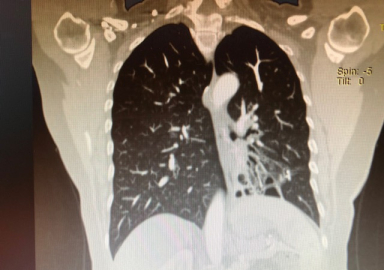

Konu ile ilgili bilgi veren Göğüs Cerrahisi Uzmanı Doç. Dr. Özkan Demirhan,” Soluk borusunun devamında ana bronş ve sonrasında bronşlar gelmektedir, bronş duvarının kas ve elastik yapısının bütünlüğünün bozulması sonucunda anormal ve kalıcı genişlemeye Bronşektazi denir. Bronşektazi doğumsal nedenlerden kaynaklanabileceği gibi sonradan da oluşabilir. Doğumsal nedenlerden kaynaklı Bronşektazi'de anatomik bozukluklar, damarsal bozuklular, solumun yolu üzerindeki silia tabakası bozuklukları ve immün sistem zayıflıkları rol oynar. Sonradan gelişen Bronşektazi'de ise sigaranın olumsuz etkilerinin yanı sıra sık geçirilen akciğer enfeksiyonları, bronşu tıkayan (yabancı cisim), bronşu daraltan durumlar ( bronş etrafında bulunan lenf bezelerinin bası yapması), aspirasyon pnömonisi gibi durumlar söz konusu olabilir. Bronşektazi en sık sol alt lobda görülmesine rağmen akciğerin tüm bronşlarını etkileyebilir” dedi.